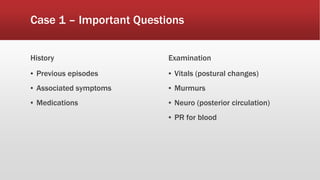

This document discusses various cases of collapse and syncope. It defines collapse as transient loss of consciousness with loss of postural tone and full recovery. Syncope is defined as loss of postural tone with or without loss of consciousness and full recovery. It then discusses the multiple potential causes of collapse and syncope including toxicological, cardiac conduction abnormalities, structural cardiac issues, autonomic dysfunction and more. It then goes through 9 case examples, discussing important questions to ask, potential tests and interventions for each case.